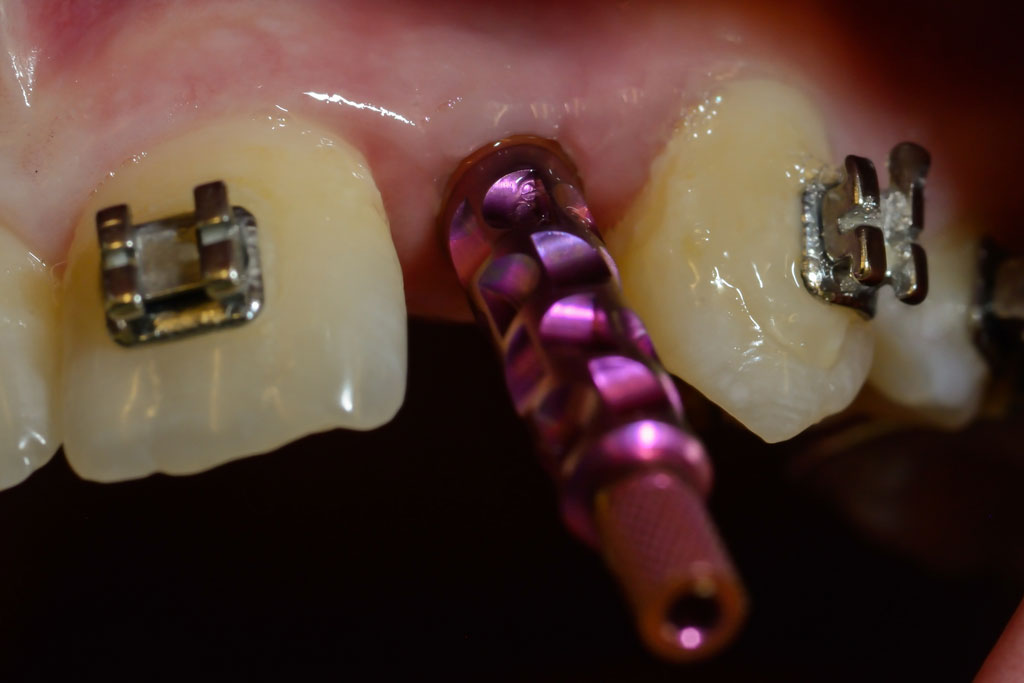

Die Nichtanlage der seitlichen oberen Schneidezähne und der zweiten unteren kleinen Backenzähne (Prämolaren) ist relativ häufig.

Wir verfügen über eine jahrzehntelange Erfahrung in der kieferorthopädischen Vorbehandlung, Implantologie und der prothetischen Versorgung von Nichtanlagen, sowie der Chirurgie und der Einordnung von verlagerten bleibenden Zähnen ohne den Einsatz von Implantaten.